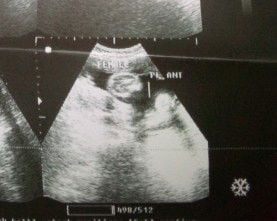

Ultrasound gender

Possible pba na Mali Ang ultrasound Kasi po nag paultrasound ako ng 5months chan ko Ang sbe boy..umasa ako tpos ngyong mag 8months nag paultrasound ako sbe nmn girl..tingin nyo po Tama ba Ang sa ultrasound?#advicepls #respect_post#pregnancy #pleasehelp